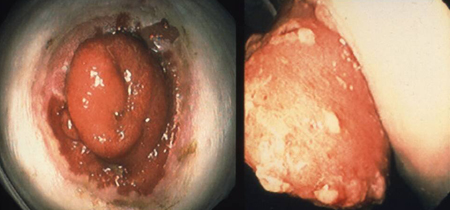

[Figure caption and citation for the preceding image starts]: Brooke ileostomy in familial adenomatous polyposis: adenoma riskFrom the personal collection of Lisa A. Boardman, MD; used with permission [Citation ends].